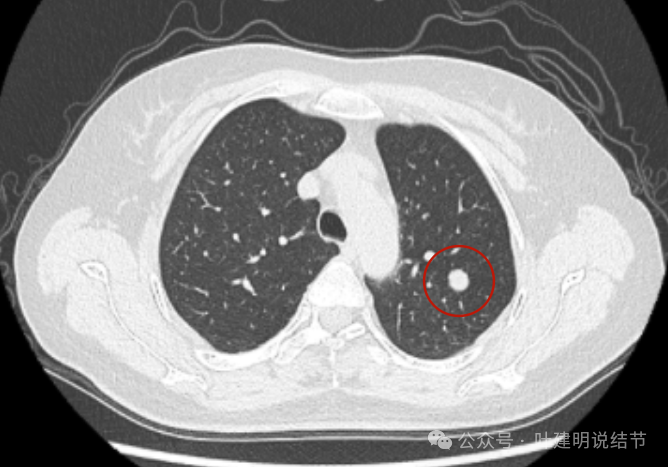

2019年5月时左上叶实性结节,边缘很光滑,没有毛刺或血管征,影像上看像良性的。

2019年10月,变化不大,但这个层面看略显得有膨胀感。